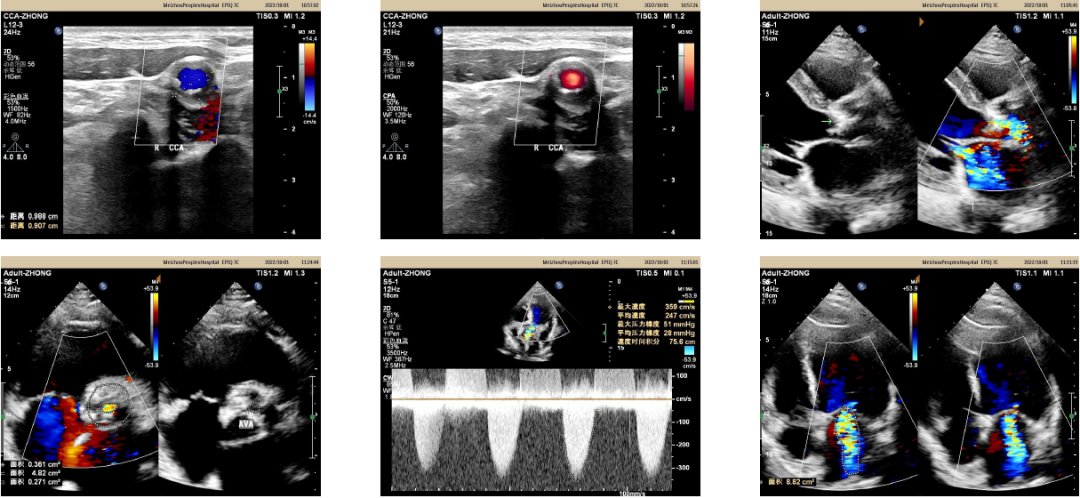

主动脉根部解剖及入路分析

术前钟志雄教授组织多学科会诊,认为患者心衰由严重心脏瓣膜及冠脉疾病引起,符合TAVR+PCI一站式手术指征;同时,患者主动脉瓣狭窄属于低压差低流速这种高危类型,且心功能低,极易出现术中循环奔溃的风险,在ECMO支持下行TAVR+PCI一站式手术是更优更安全的方案;由于股动脉入路至主动脉弓存在弥漫性钙化,斑块脱落及血管夹层风险高,综合考虑采用右颈动脉入路作为主入路。

出院前超声